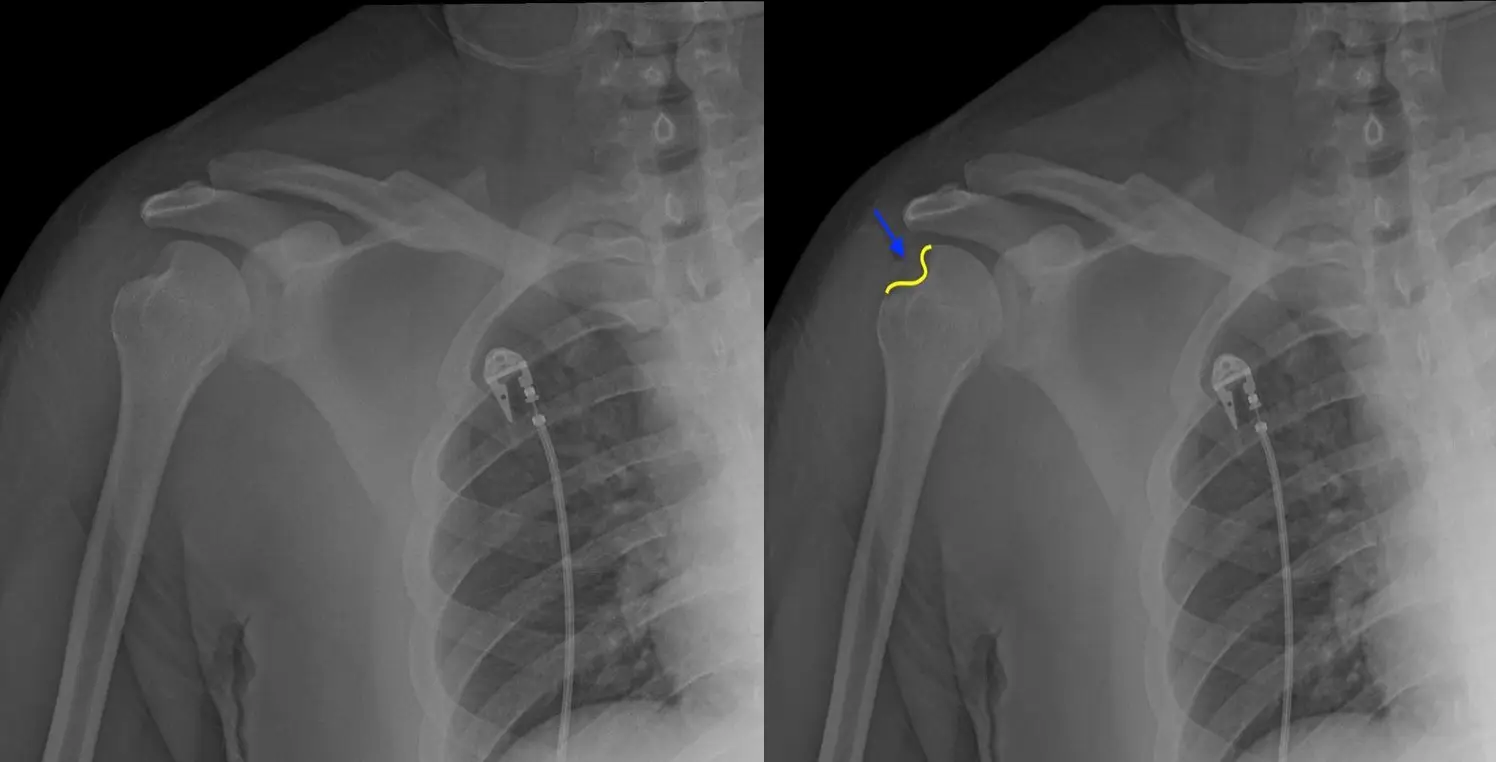

Hill Sachs lezyonu, kol kemiği (humerus) başının posterolateral kısmında kortikal çöküntü oluşması ile karakterize bir omuz yaralanmasıdır. Bu durum, genellikle anterior omuz çıkıkları sırasında meydana gelir. Özellikle humerus başı, glenoidin anteroinferior kenarına şiddetli bir şekilde çarptığında, kemikte kalıcı çöküntü oluşur.

Hill Sachs lezyonu, çoğunlukla bankart lezyonu ile birlikte ortaya çıkar. Bankart lezyonu, glenoidin anteroinferior kısmında oluşan bir yırtığı ifade eder ve Hill Sachs ile birlikte omuzun kronik instabilitesine yol açabilir.

Bu lezyon genellikle omuzun içe dönme hareketi sırasında daha belirgin hale gelir ve doğru şekilde teşhis edilmesi önemlidir. Bilgisayarlı tomografi (BT) veya MR görüntüleme ile kolun hareketi sırasında eklem yüzeyleri detaylı şekilde incelenebilir.